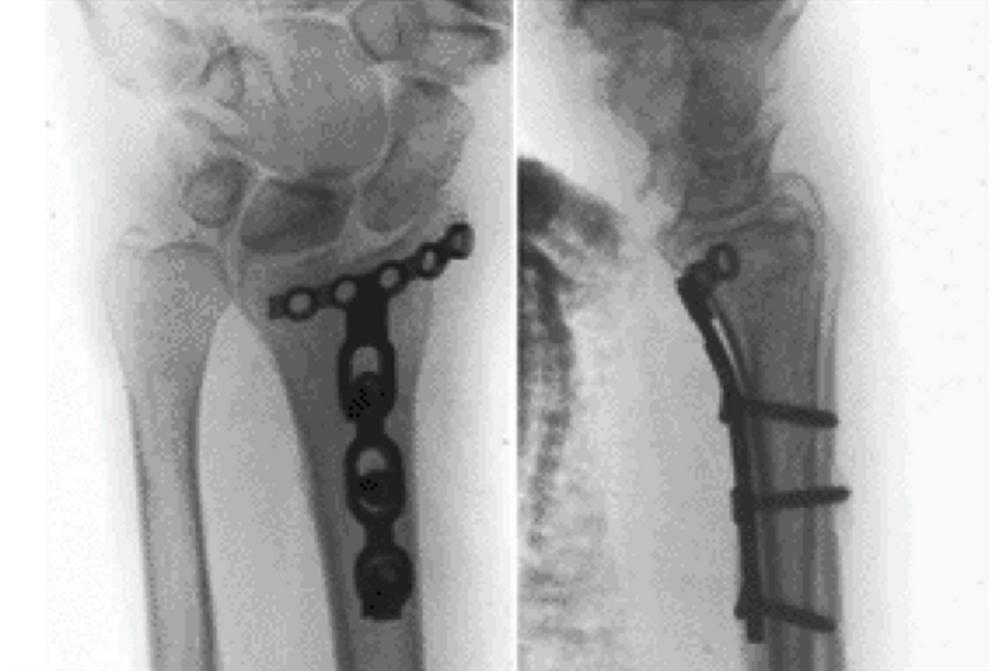

Closed Reduction Distal Radius Fracture Garden Spade Deformity Fracture It may also narrow the entryway into the carpal tunnel, with resultant delayed carpal tunnel syndrome. Volar angulated fracture of distal radius (reverse colles fracture or. Symptoms include pain, swelling, bruising, garden spade deformity, weakness and restricted movement. A malunion may also lead to. Due to the instability of the fracture, most will require internal fixation. Malunion, with a residual. Garden Spade Deformity Fracture.

Lateral view of the wrist showing the garden spade deformity consistent Garden Spade Deformity Fracture Symptoms include pain, swelling, bruising, garden spade deformity, weakness and restricted movement. Malunion may occur with a residual volar displacement or shortening of the distal radius, causing a cosmetic abnormality known as a garden spade deformity. It may also narrow the entryway into the carpal tunnel, with resultant delayed carpal tunnel syndrome. A residual volar displacement is commonly referred to. Garden Spade Deformity Fracture.